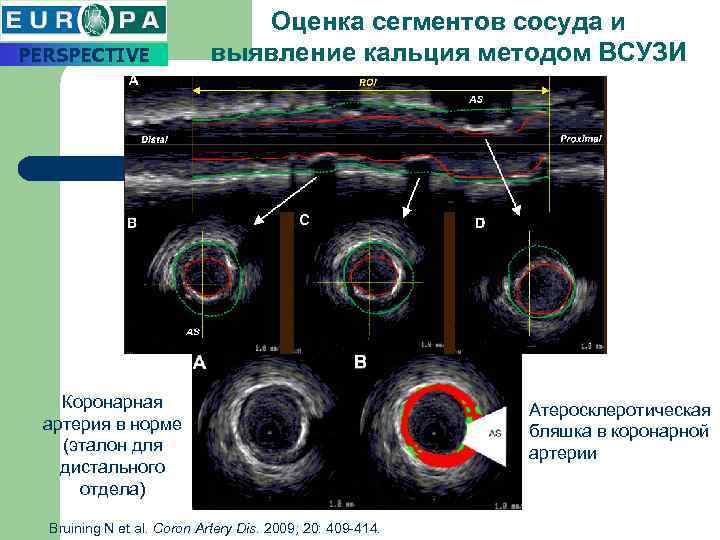

PERSPECTIVE Оценка сегментов сосуда и выявление кальция методом ВСУЗИ Коронарная артерия в норме (эталон для дистального отдела) Bruining N et al. Coron Artery Dis. 2009; 20: 409 -414. Атеросклеротическая бляшка в коронарной артерии